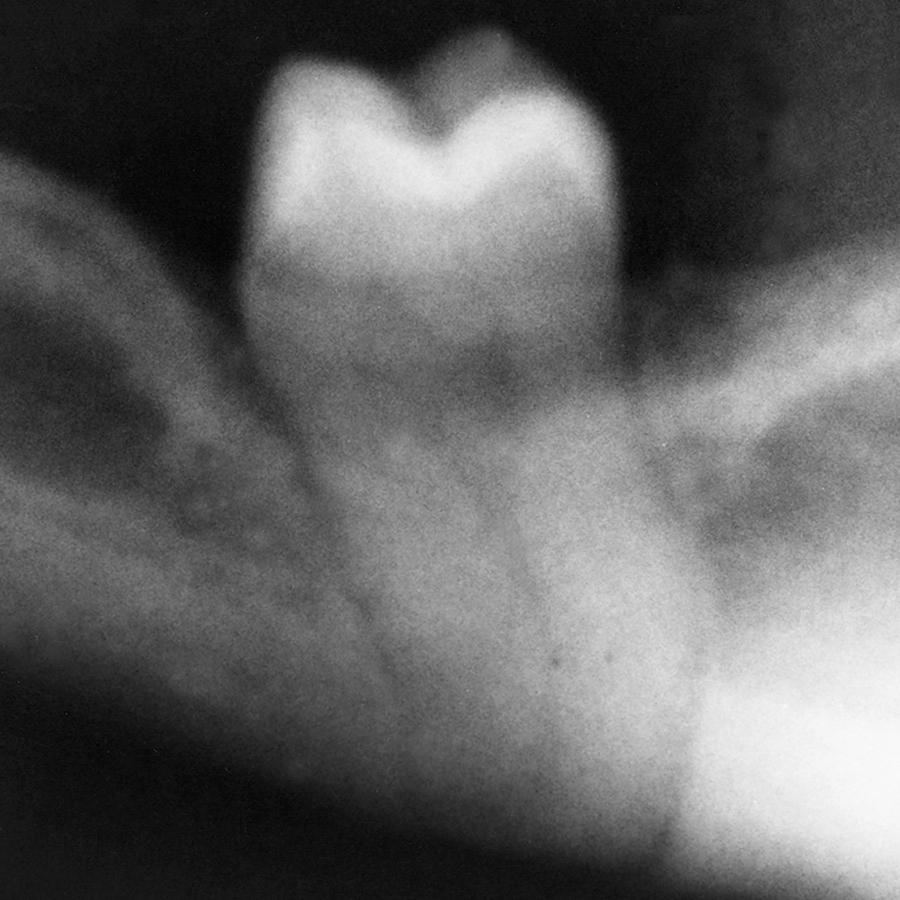

An impacted third molar in the mandible occupies space that is usually filled with bone. This weakens the mandible and renders the jaw more susceptible to fracture at the site of the impacted tooth ( Fig. 10.14 ). If the jaw fractures through the area of an impacted third molar, the impacted third molar is frequently removed before the fracture is reduced, and fixation is applied (see Chapter 24 ).

Fig. 10.14, Fracture of a mandible, which occurred through the location of an impacted third molar.